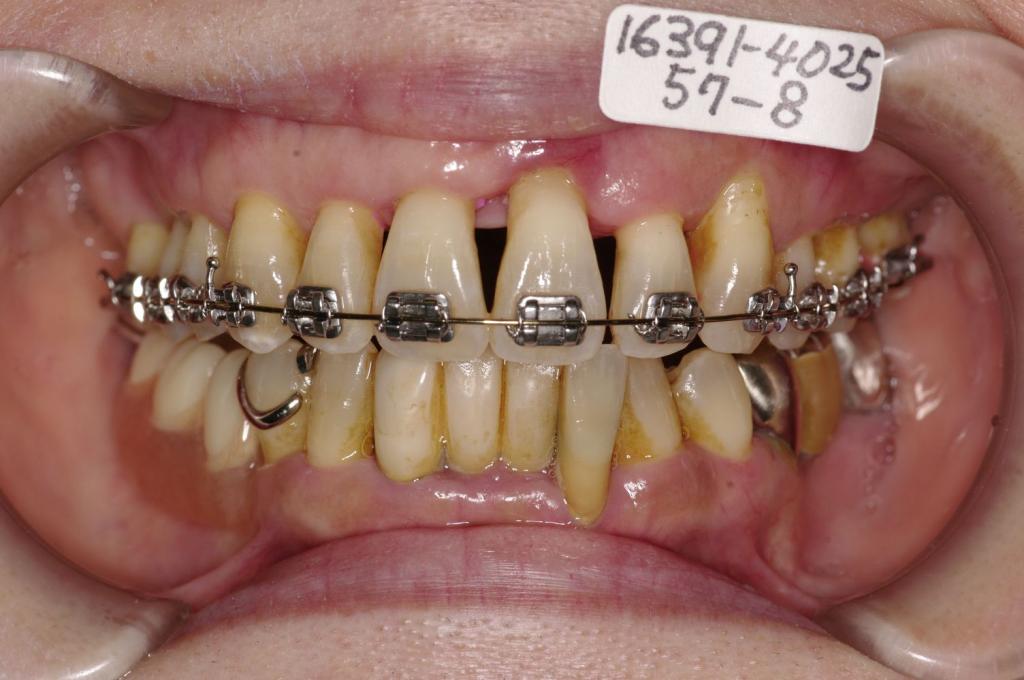

装置の種類及び治療法 診断:叢生 歯周病

治療方法および装置:上顎のみマルチブラケット装置

抜歯:非抜歯

欠損歯:右上86 /左上68

右下765 /左下6

治療期間:7ヶ月

装置写真

治療前

歯並び・咬み合わせ・八重歯・乱杭歯の矯正治療前口内写真NO.1210